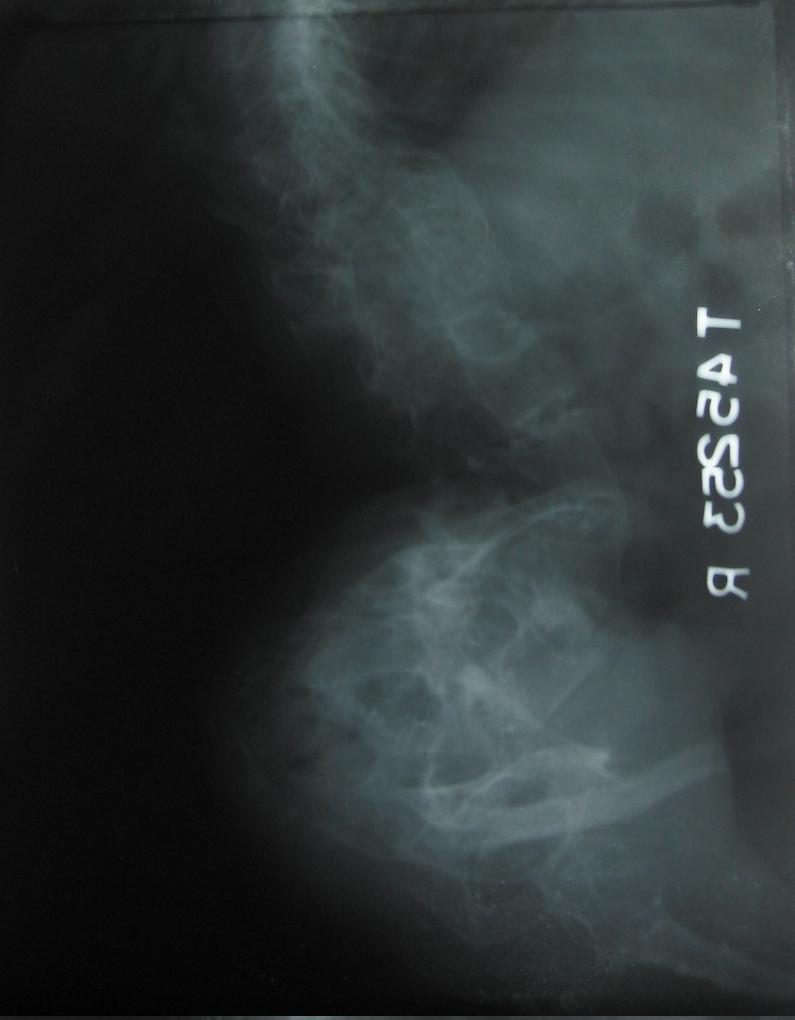

Fig.4